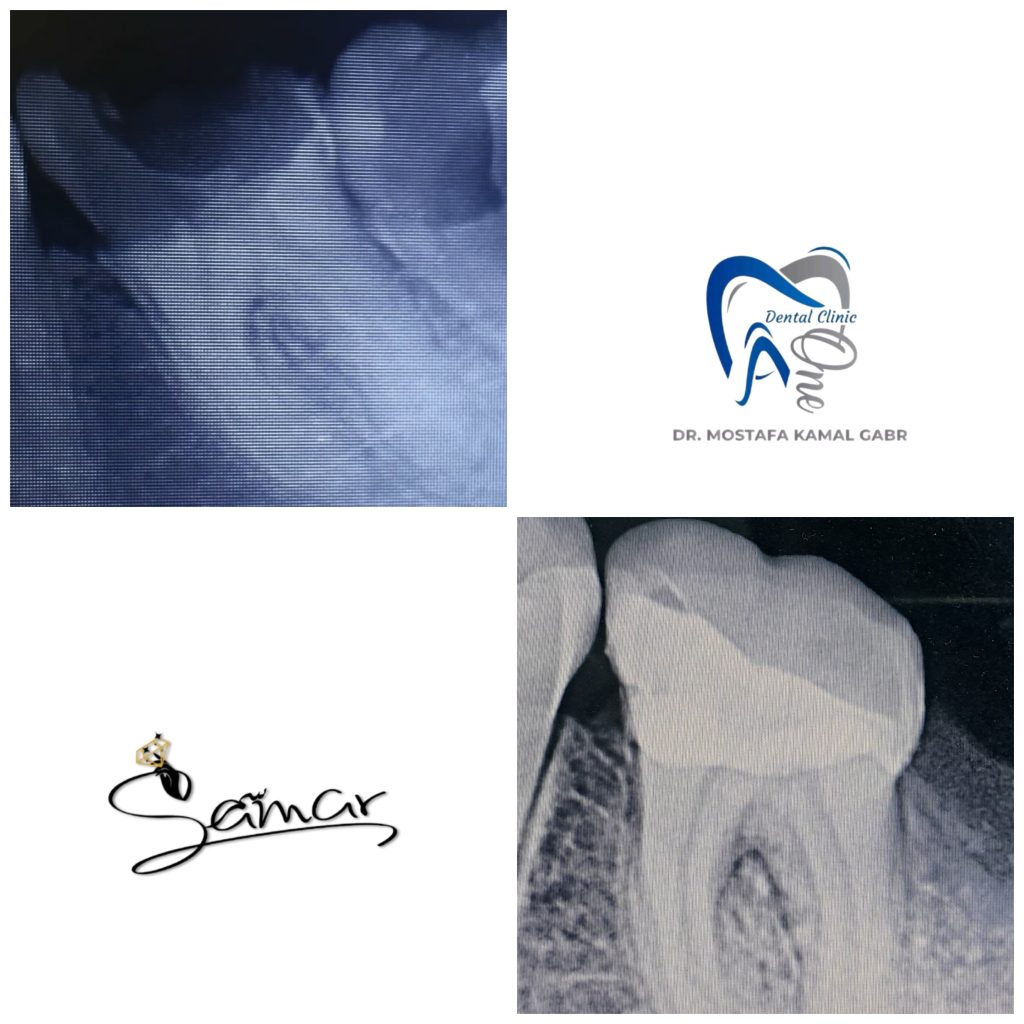

Final post operative and Radiograph veiw

pre and post periapical radiograph